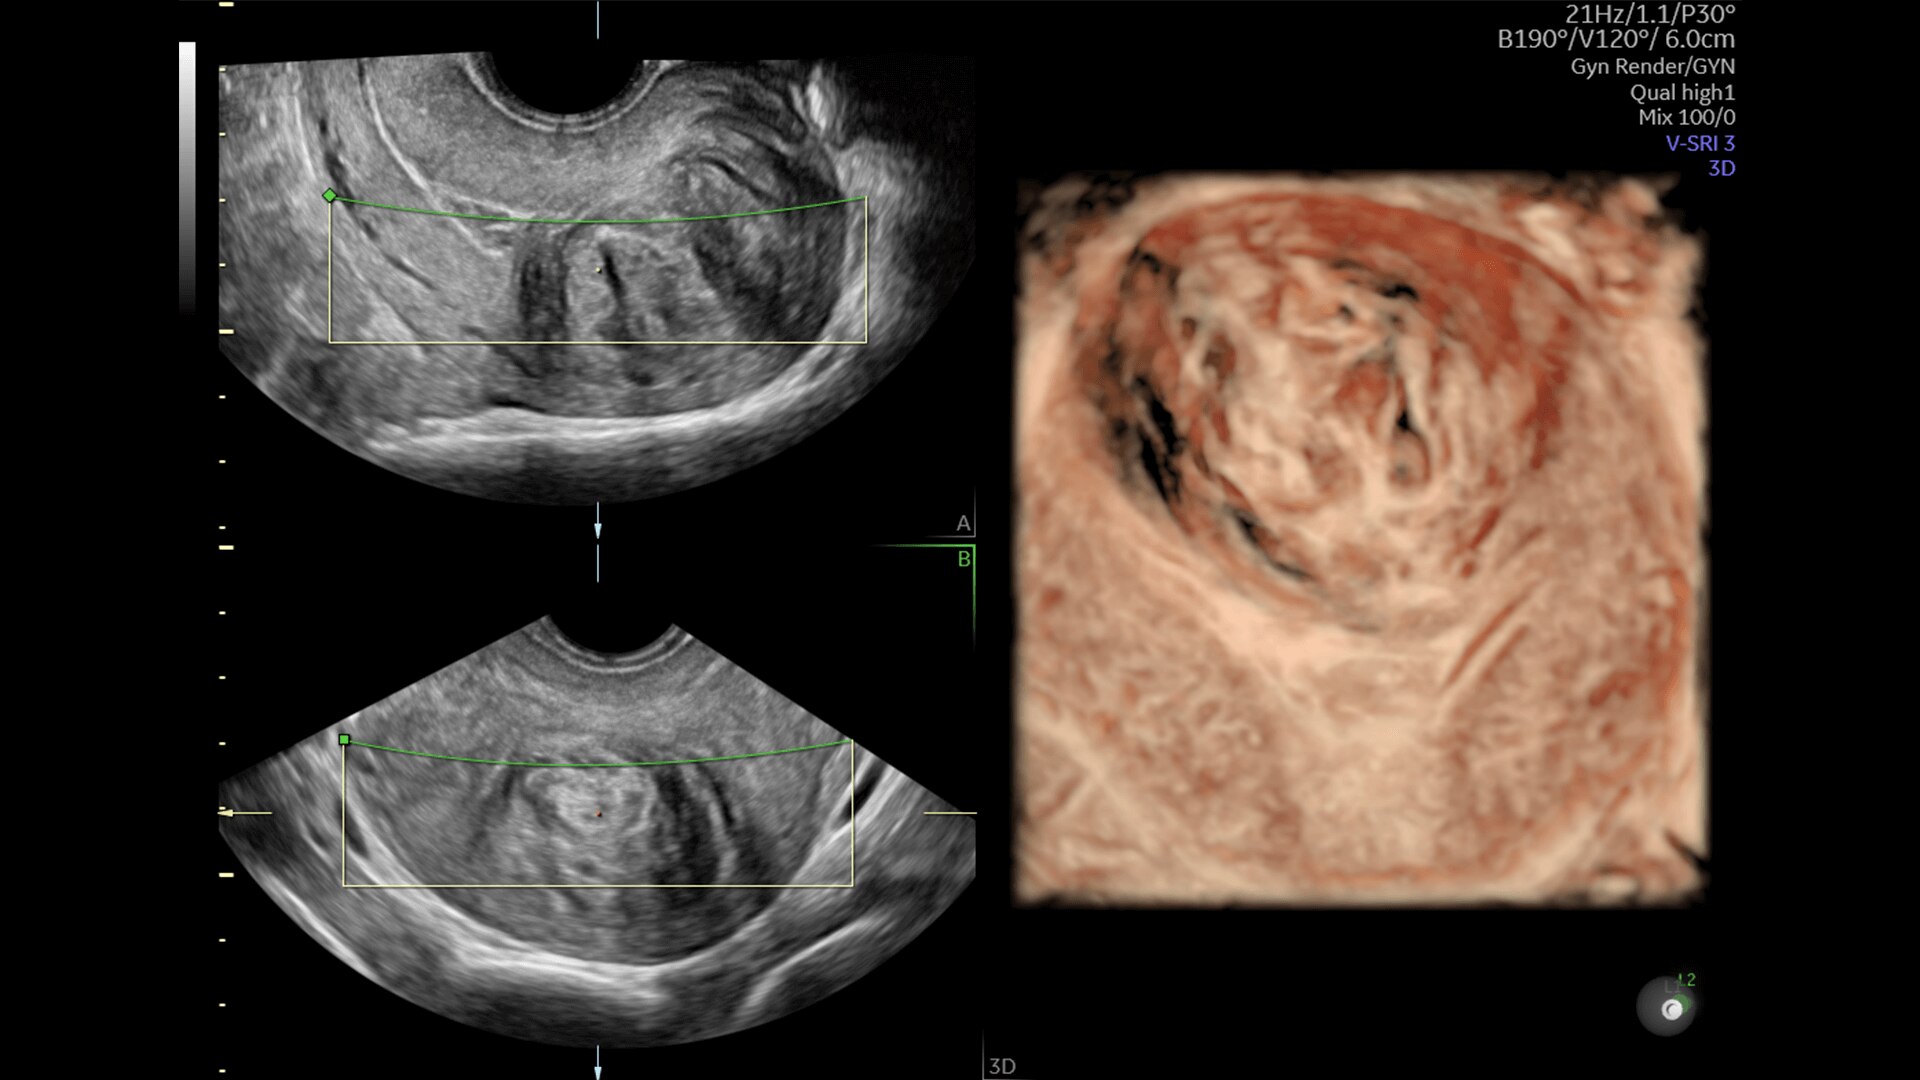

Pelvic Health

Offer patient answers faster with Ai-based automation tools